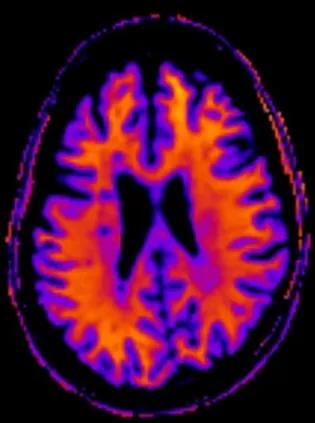

Multiple sclerosis is a chronic disease associated with progressive loss of myelin, the natural insulator of nerves. HTML OverviewMultiple sclerosis (MS) is a chronic inflammatory disease of the central nervous system, characterised by demyelination and axonal damage. Patients may present with a wide range of symptoms, such as vision problems, muscle spasms, mobility impairment, cognitive dysfunctioning and fatigue. The age of onset of symptoms generally lies between 20 to 40 years. MS may present with an immediate progressive disease course – primary progressive MS – or with a relapsing-remitting disease course that usually results in a progressive course – secondary progressive MS - at later stages.Together with the Anne Rowling Clinic at the University of Edinburgh we study patients with relapsing-remitting MS and primary progressive MS. The aim is to aid patient treatment by means of better early disease stratification for treatment with existing and new therapies. Patients included in these studies receive an extensive range of assessments, including brain and retinal imaging, and cognitive, inflammatory markers and genetic tests, that will help map the disease from multiple perspectives. Using quantitative brain imaging, we aim to develop biomarkers that aid prediction of clinical disability over time, or that act as reliable measures of disease status. Additionally, they are used to test drug effectiveness and may aid explanation of some biological processes underlying MS. In addition to quantifying MS lesions and brain volume using standard structural MRI we are also using diffusion tensor imaging (DTI) and magnetisation transfer (MT) imaging. These techniques are able to detect subtle brain abnormalities that we cannot detect using conventional imaging techniques; in particular the integrity of myelin, which is critical for nerve function and a hallmark of damage in MS. Lead MS researcher Prof Adam WaldmanTo discuss new research & collaborative imaging projects with Edinburgh Imaging, please contact: Edinburgh Imaging Enquiries: studies / collaborations / facilities Contact details Email: edimg.studyinfo@ed.ac.uk Research staff with a MS focusDr Mark BastinDr Maria Valdés HernándezDr Rozanna MeijboomDr Michael ThrippletonDr Beth YorkDr Adriana TavaresDr Catriona WimberlyDr Joana LeitaoAgniete Kampaite Current projectsCompleted projects Funding organisations & groupsOrganisations are listed alphabetically:Anne Rowling ClinicBiogenChief Scientist Office Medical Research Council (MRC)MS societyNational Institute for Health Research (NIHR)National Institute for Health Research University College London Hospitals Biomedical Research CentreSanofiStratified Medicine ScotlandUniversity College LondonUniversity of Edinburgh Relevant links MS Society Edinburgh Centre for MS ResearchFuture MS studyFuture MS study 2Multiple Sclerosis imaging group twitter15 Feb 22. FutureMS-2 imaging begins04 Feb 22. Dr Beth York gains PhD19 Feb 21. Edinburgh Centre for MS Research Relevant Edinburgh Imaging publications 07 Apr 22. Featured Paper. Quantitative magnetisation transfer imaging in relapsing-remitting multiple sclerosis: a systematic review and meta-analysis10 Nov 21. Featured Paper. MRI-derived g-ratio & lesion severity in newly diagnosed multiple sclerosis01 Nov 21. Featured Paper. Rim lesions are demonstrated in early relapsing–remitting multiple sclerosis using 3 T-based susceptibility-weighted imaging in a multi-institutional setting09 Sep 21. Featured Paper. The prevalence of paramagnetic rim lesions in multiple sclerosis: A systematic review & meta-analysis03 May 18. Featured paper. Small vessels, dementia & chronic disease19 May 17. Featured Paper. The clinico-radiological paradox of cognitive function & MRI burden of white matter lesions in people with multiple sclerosis: A systematic review & meta-analysisPlease view all our publications, here Relevant publications Lema A, et al., A comparison of magnetization transfer methods to assess brain & cervical cord microstructure in multiple sclerosis, J Neuroimaging 2017 27:221-226. doi:10.1111/jon.12377Bishop CA, et al., Analysis of ageing-associated grey matter volume in patients with multiple sclerosis shows excess atrophy in subcortical regions, Neuroimage Clin. 2016 Nov 9;13:9-15. eCollection 2017Mattoscio M, et al., Hematopoietic mobilization: Potential biomarker of response to natalizumab in multiple sclerosis, Neurology. 2015 (14):1473-82. doi: 10.1212/WNL.0000000000001454Newbould RD, et al., Age independently affects myelin integrity as detected by magnetization transfer magnetic resonance imaging in multiple sclerosis, Neuroimage ClinMollison D, et al., The clinico-radiological paradox of cognitive function and MRI burden of white matter lesions in people with multiple sclerosis: A systematic review and meta-analysis, PLoS One. 2017 (5):e0177727. doi: 10.1371/journal.pone.0177727 Marshall I, et al., Characterisation of tissue-type metabolic content in secondary progressive multiple sclerosis: a magnetic resonance spectroscopic imaging study, J Neurol. 2018 (8):1795-1802. doi: 10.1007/s00415-018-8903-yMatthews PM, et al., A practical review of the neuropathology and neuroimaging of multiple sclerosis, Pract Neurol. 2016 Aug;16(4):279-87. doi: 10.1136/practneurol-2016-001381Politis M, et al., Increased PK11195 PET binding in the cortex of patients with MS correlates with disability, Neurology. 2012 (6):523-30. doi: 10.1212/WNL.0b013e3182635645. This article was published on 2024-08-22